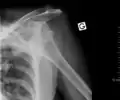

Lightbulb sign indicative of posterior shoulder dislocation shown on the left. On the right, the same shoulder after reduction.

Posterior dislocations are uncommon, and are typically due to the muscle contraction from electric shock or seizure.[6] They may be caused by strength imbalance of the rotator cuff muscles. People with dislocated shoulders typically present holding their arm internally rotated and adducted, and exhibiting flattening of the anterior shoulder with a prominent coracoid process.

Posterior dislocations may go unrecognized, especially in an elderly person[12] and in people who are in the state of unconscious trauma.[13] An average interval of 1 year was noted between injury and diagnosis in a series of 40 people.[14]